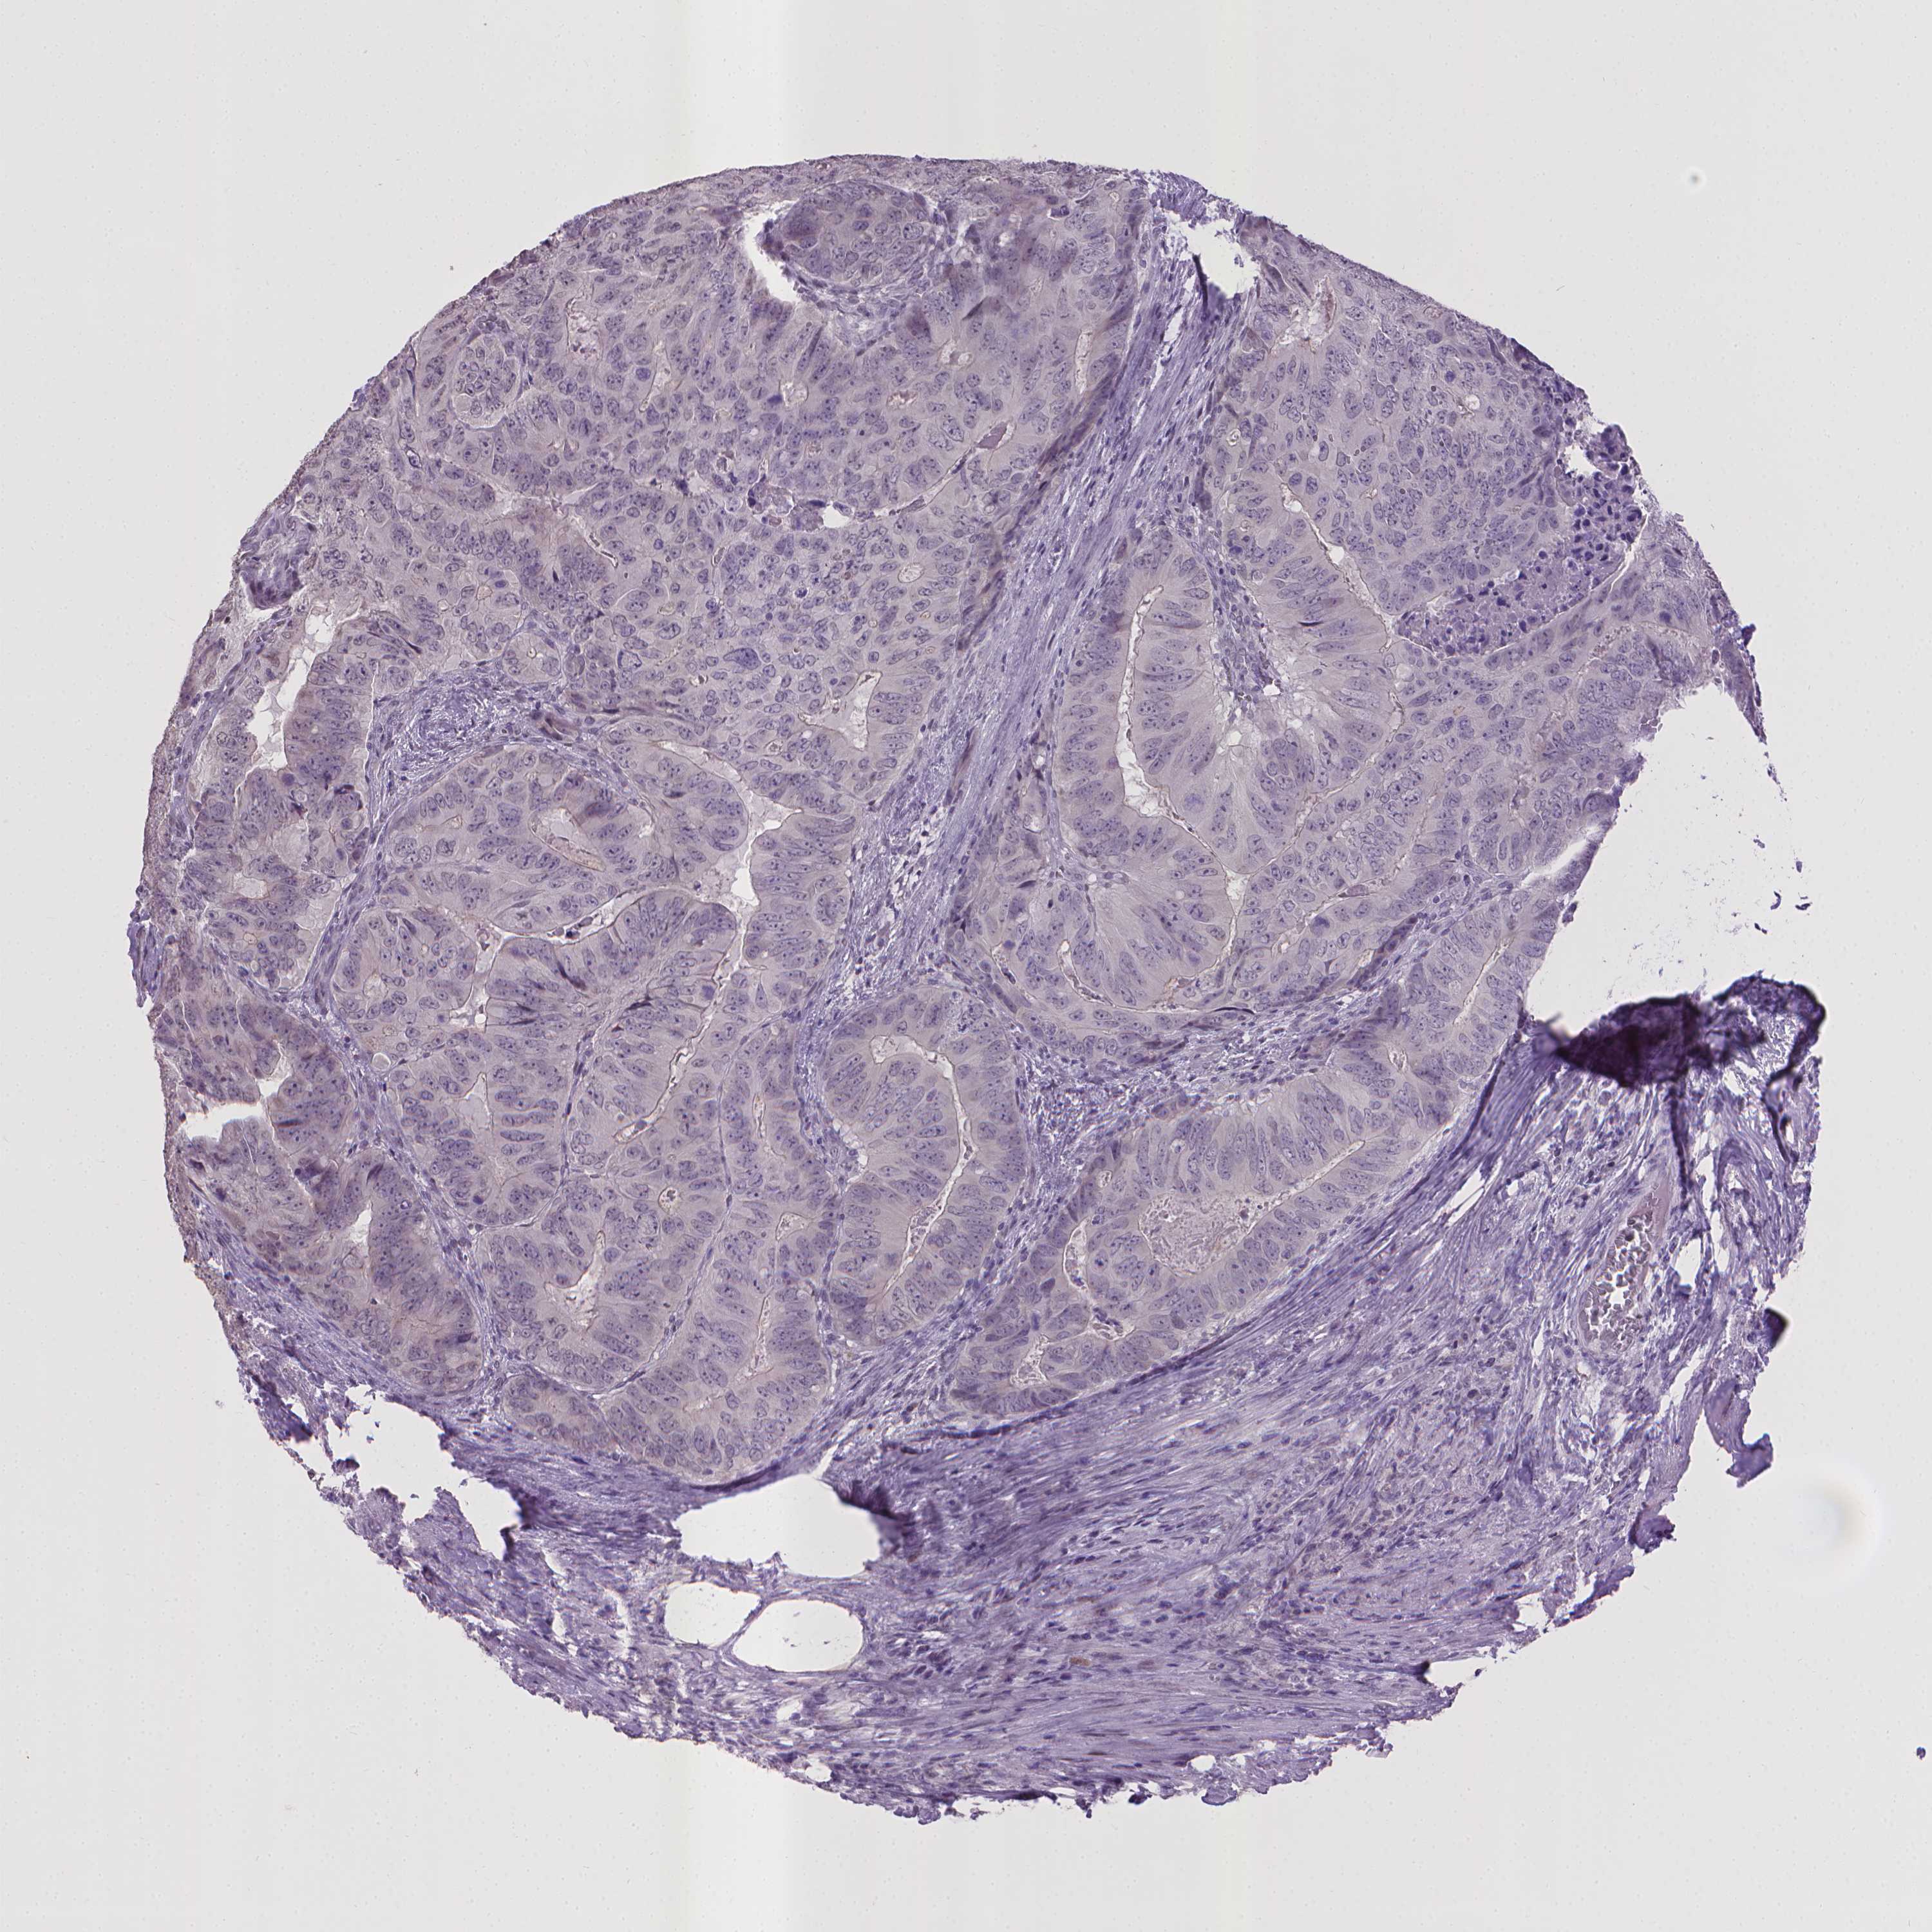

CANCER COLORECTAL CANCER Show tissue menu

Colorectal cancer

Human cancer